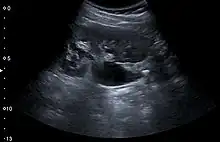

Renal ultrasonography can sometimes be useful, because it gives details about the presence of hydronephrosis, suggesting that the stone is blocking the outflow of urine.[58] Radiolucent stones, which do not appear on KUB, may show up on ultrasound imaging studies. Other advantages of renal ultrasonography include its low cost and absence of radiation exposure. Ultrasound imaging is useful for detecting stones in situations where X-rays or CT scans are discouraged, such as in children or pregnant women.[66] Despite these advantages, renal ultrasonography in 2009 was not considered a substitute for noncontrast helical CT scan in the initial diagnostic evaluation of urolithiasis.[65] The main reason for this is that, compared with CT, renal ultrasonography more often fails to detect small stones (especially ureteral stones) and other serious disorders that could be causing the symptoms.[14]

On the contrary, a 2014 study suggested that ultrasonography should be used as the initial diagnostic imaging test, with further imaging studies be performed at the discretion of the physician on the basis of clinical judgment, and using ultrasonography rather than CT as an initial diagnostic test results in less radiation exposure and equally good outcome.[67]

Renal ultrasonograph of a stone located at the pyeloureteric junction with accompanying hydronephrosis.